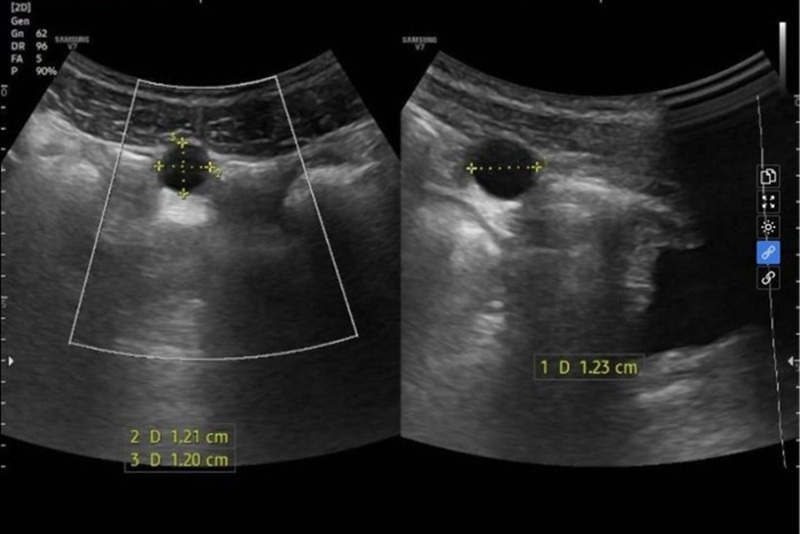

Siêu âm ổ bụng phát hiện ở sát thành bụng vùng hạ vị có một cấu trúc dạng nang kích thước khoảng 12x12mm, ranh giới rõ với bàng quang. Chẩn đoán theo dõi nang mạc treo vùng hạ vị.

Siêu âm ổ bụng cho kết quả theo dõi nang mạc treo vùng hạ vị